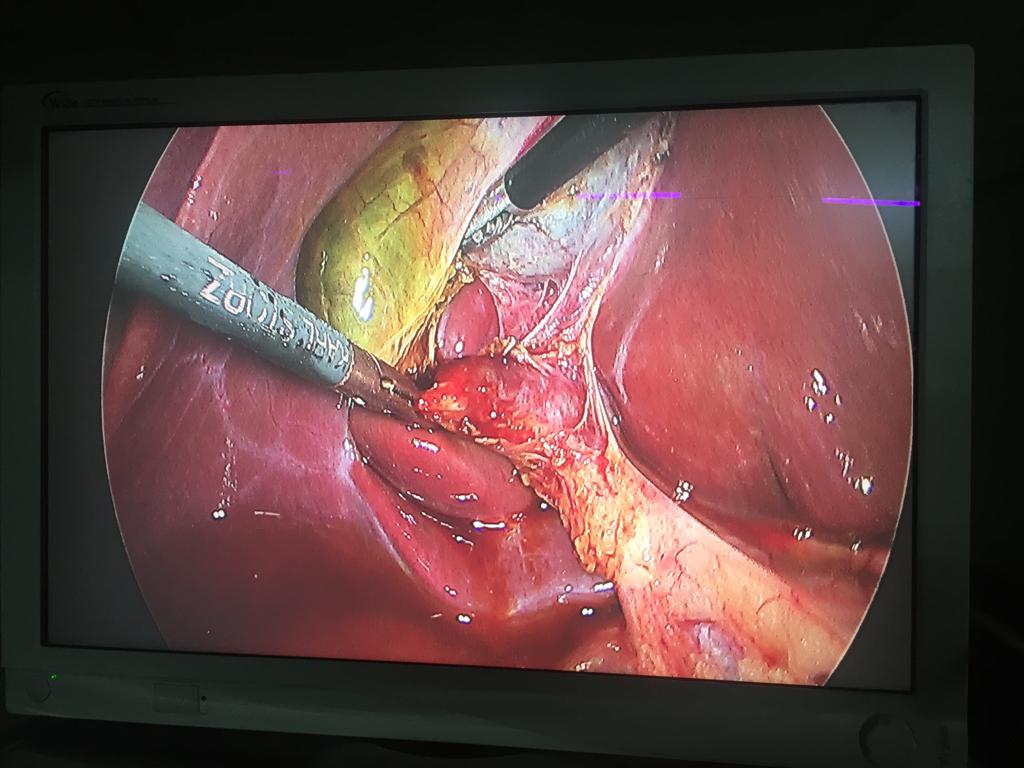

Acute Cholecystis, Mucocele Gallbladder with big stone at the neck. Completely done Laparoscopically